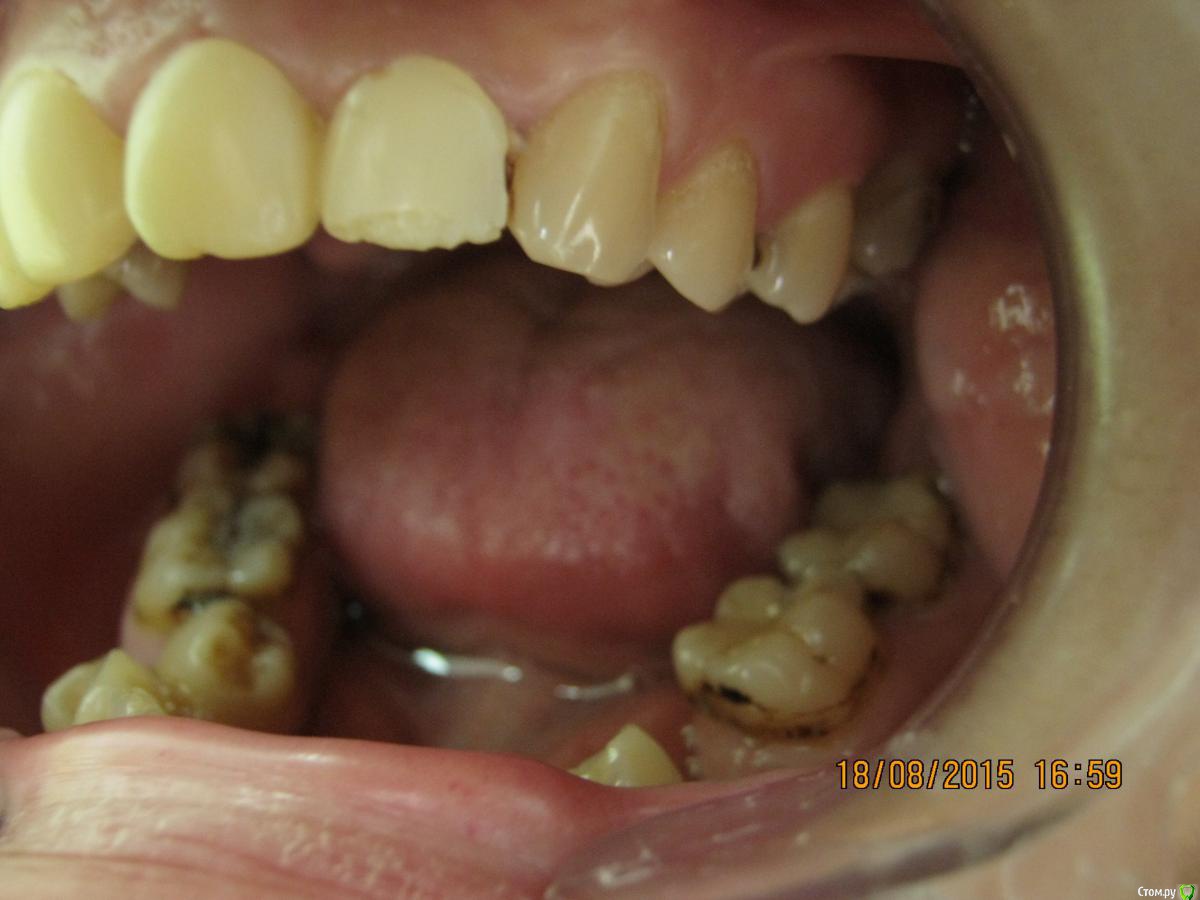

SeregaStomatolog Опубликовано 18 августа, 2015 Поделиться Опубликовано 18 августа, 2015 Добрый вечер уважаемые коллеги!В клинику обратилась пациентка с такой ситуацией во рту.Подскажите пожалуйста что можно сделать и с чего начать. Ссылка на комментарий

krokomot Опубликовано 18 августа, 2015 Поделиться Опубликовано 18 августа, 2015 Бюджет не очень большой,в пределах 50-70 т.р для такого рода патологии как-то уж совсем мало, тут еле в съемники с пару коронками влезешь. Налицо вторичные деформации, десневая улыбка у пациентки и проблемы с периодонтом*, весь букет)) А что хочет пациентка?, уж не голивуд ли?)) Ссылка на комментарий

SeregaStomatolog Опубликовано 18 августа, 2015 Автор Поделиться Опубликовано 18 августа, 2015 Сделав как хочет пациентка вы не получите красивый результат, которого она ждет! и получится что вы не смогли реализовать ее мечты , а значит доктор неахти)) да и вы не особо результатом будете довольны, вам это надо? Если в эстетике проблем нет, восстановите функцию. Ненужное удалить, длинные зубы дэпульпировать, укоротить ну и коронуйте))Мне кажется если я возьмусь,то все равно не буду результатом доволен,т.к. все реализовать не получится.Самая большая проблема в области отсутствующих 1.6,1.7-зубо-альвеолярное удлинение 4.6,4.7 настолько велико,что они практически касаются слизистой в области 1.6,1.7. Ссылка на комментарий